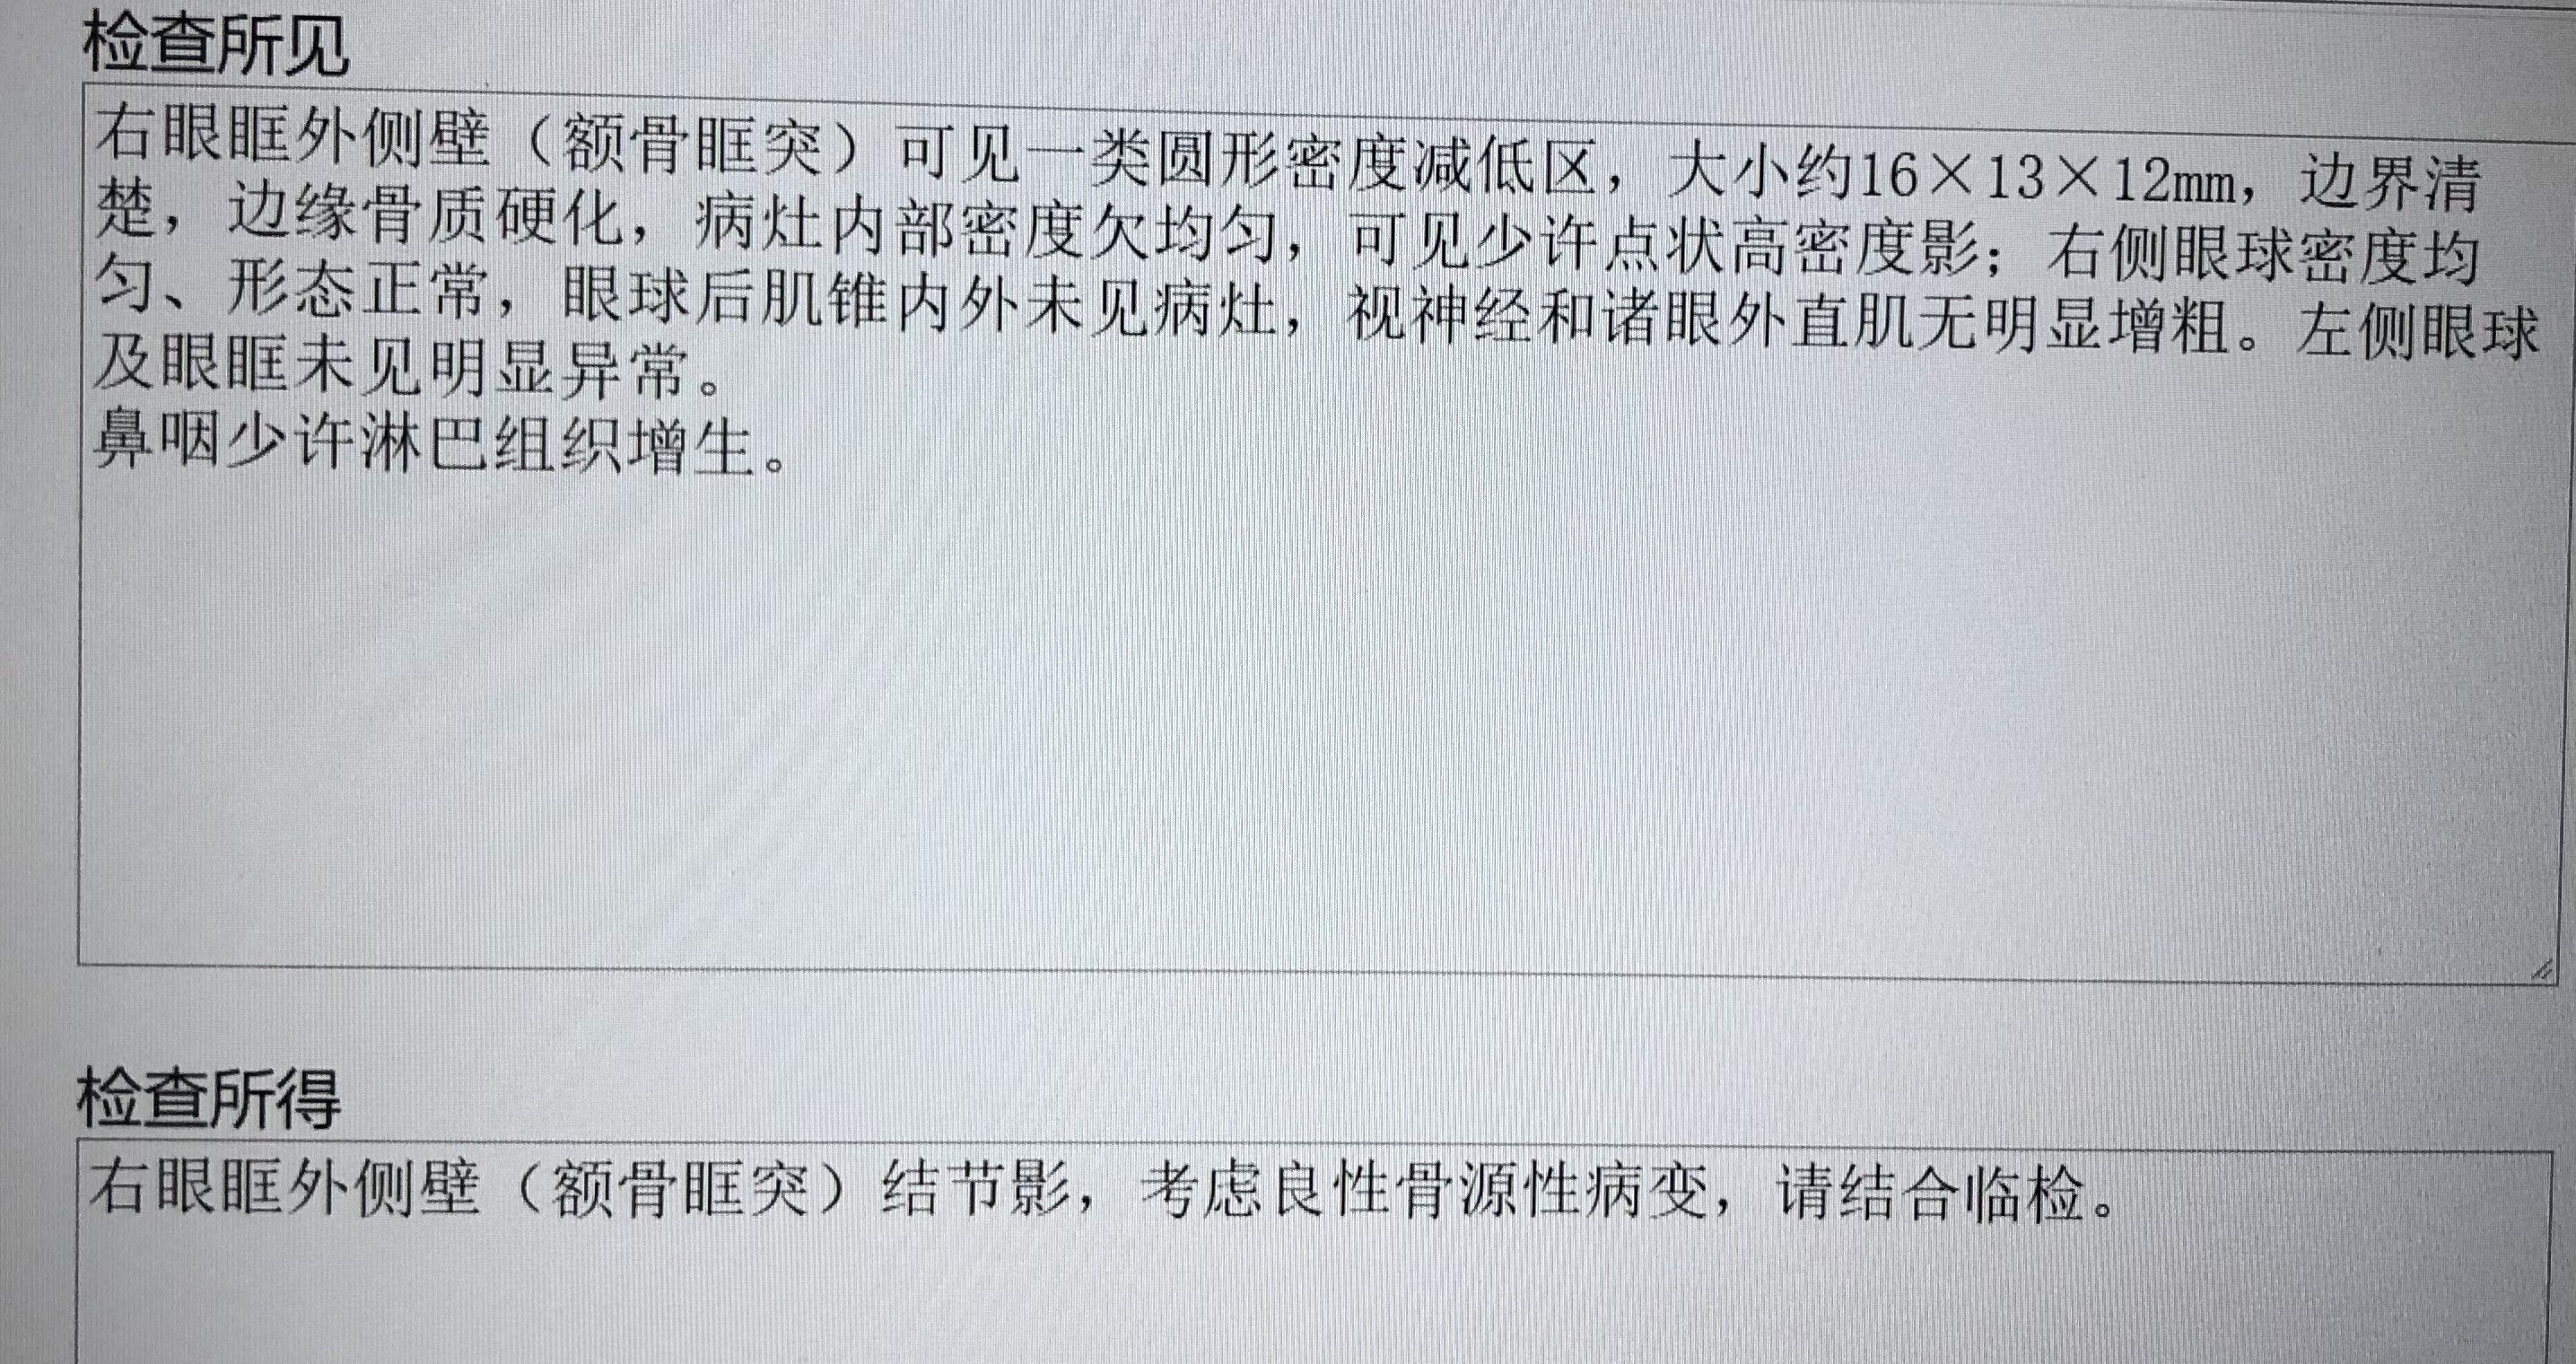

本例患者,对比双侧眼眶,可见右眼外上方骨壁增厚,骨性结构内有低信号病灶,

病灶无论在CT和核磁共振上都会显影,考虑到疼痛症状始终不缓解,最终决定手术明确性质。

核磁共振对应部位可见病变